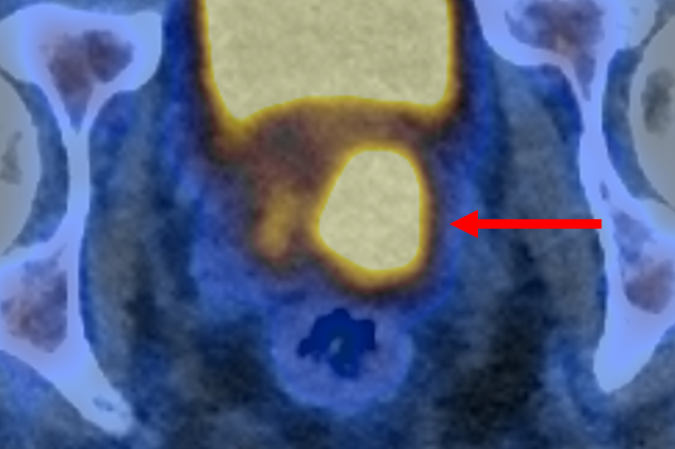

O exame PET/CT (tomografia por emissão de Pósitrons/tomografia computadorizada) com PSMA identifica células agressivas presentes na próstata, que são potencialmente prejudiciais e podem precisar de tratamento. Isso é possível graças a uma molécula que se liga a essas estruturas e as faz brilhar, aparecendo como pontos luminosos na imagem. O estudo afirma que isso também pode ajudar a reduzir o risco de sobrediagnóstico.

O ensaio descobriu que a tomografia por emissão de pósitrons (PET/CT) com PSMA podia identificar pessoas que não tinham câncer ou cujo tumor era de tão baixo risco e com crescimento tão lento que provavelmente nunca causaria danos. Esses pacientes não precisaram de biópsia. A nova abordagem reduziu pela metade o número de pessoas submetidas ao exame invasivo, sem deixar de detectar nenhum câncer maligno.